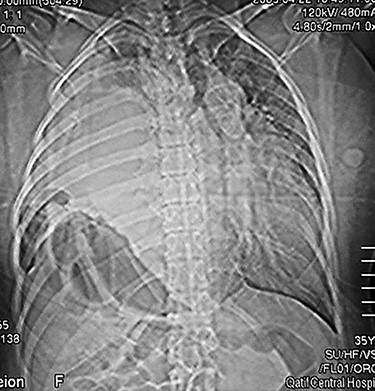

The patient was prepared for surgery. The chest was opened through a right posterolateral thoracotomy. The right hemi-diaphragm was found to be absent and the liver was lying high up in the right thorax with its inferior surface adherently facing the pericardium. The right lung was collapsed, and the transverse colon and the stomach were also found in the right hemi-thorax inferiorly. The liver was carefully mobilized from the pericardium and the herniated organs were successfully reduced into the abdomen. After excision of the thin hernia sac, the right diaphragm was reconstructed using a polypropylene mesh. The right lung expanded well at the end of the procedure. Postoperative chest x-ray showed full inflation of the right lung (Fig. 3).

A post-operative chest x-ray showing full inflation of the right lung.